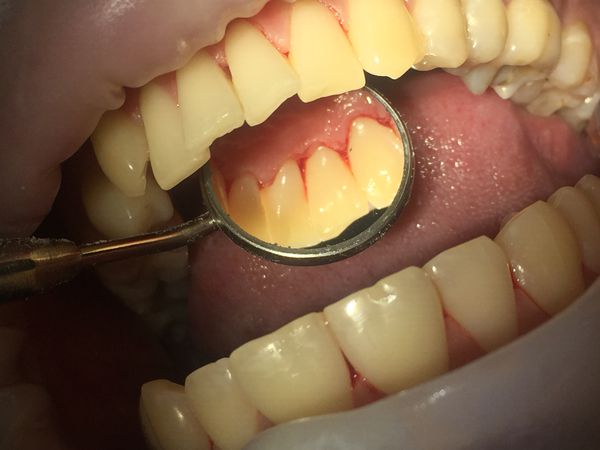

При осмотре полости рта был выявлен мягкий пигментированный зубной налёт на всех зубах верхней и нижней челюсти на язычной и нёбной поверхностях. В области передних зубов с язычной стороны визуализировался твёрдый пигментированный зубной камень. Десна и межзубные сосочки были гиперемированы (т. е. имелось покраснение) и воспалены в области всех зубов.

При осмотре с помощью стоматологического зеркала и зонда был обнаружен твёрдый зубной камень на жевательных зубах верхней и нижней челюсти справа. Непигментированный камень покрывал всю щёчную поверхность жевательных зубов верхней челюсти, при зондировании с трудом откалывался от поверхности зуба. К тому же зубной камень в области жевательных зубов верхней челюсти погружался под десну, тем самым образуя патологический карман между десной и зубом и провоцируя воспаление десны с язычной стороны. При окрашивании зубов специальными индикаторами для выявления зубного налёта был обнаружен непигментированный мягкий зубной налёт на всех зубах с вестибулярной стороны (со стороны щеки и губ).